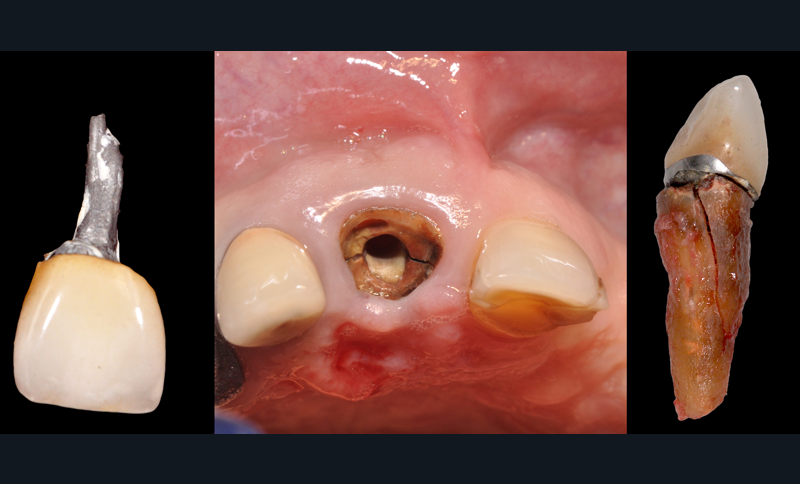

Par ailleurs, les plaignants voient souvent dans ce type de reconstitution une difficulté accrue de réalisation, avec différents écueils techniques (fig. 3).